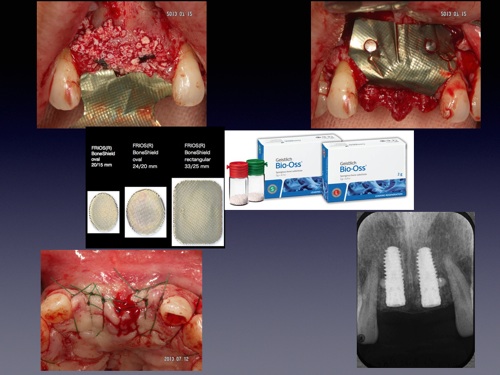

インプラント治療は、失われた歯牙を人工の歯根(チタン合金製)で再建する方法です。隣在する健康な歯を削ることが避けられる利点、かみ合わせの崩壊を防止できる利点、すでに崩壊したかみ合わせを回復できる利点、義歯の安定化が得られる利点、審美的な外観が得られる利点等、数々の利点を備えている、現在の歯科医療ではなくてならない極めて有用な治療法の一つです。

当クリニックでは安全・安心・正確なインプラント治療のためガイド手術を行っております。